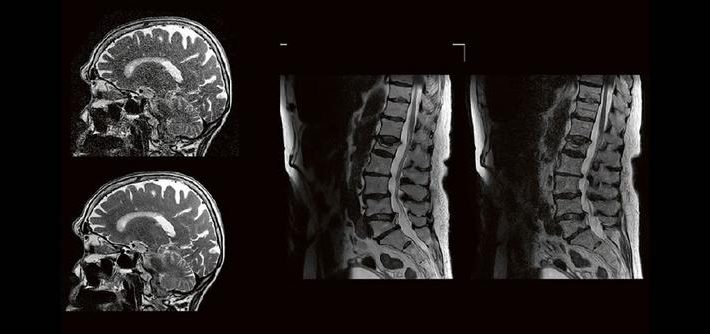

Dr. med. Urspeter Knecht Die MR-Spektroskopie – eine oft unterschätze Untersuchungsmethode – kann im Rahmen eines molekularen Fingerprints ein Game Changer sein in der neuroradiologischen Bildgebung. Eine Zusammenstellung von Hintergründen, Pitfalls, Aha-Erlebnissen, Nutzen und Risiken – Teil 2 Eventdatum: Mittwoch, 22. November 2023 17:00 – 18:00 Eventort: Online Firmenkontakt und Herausgeber der Eventbeschreibung: Canon Medical […]

Jan Hendrik Falkenstein Künstliche Intelligenz spielt in der klinischen Anwendung eine immer größer werdende Rolle. Im radiologischen Sektor erfährt besonders die Magnetresonanztomographie aktuell einen regelrechten KI-Hype. Kürzere Untersuchungszeiten, eine höhere Bildqualität oder eine Kombination aus Zeit und Qualität sind theoretisch möglich, doch ist die KI in der Praxis mehr als eine Spielerei? Wie aufwendig ist […]